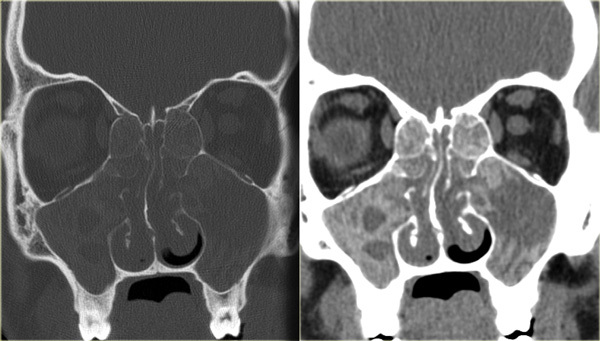

Endoscopic signs include nasal polyps , mucopurulent discharge (primarily from the middle meatus), and mucosal edema (also primarily in the middle meatus). CT findings include mucosal thickening of the paranasal sinuses and osteomeatal complex and fluid or debris in the paranasal sinuses (opacification).

These patients tend to have significant burden of polyps and over a prolonged period of time the thick, eosinophilic mucin can act as a benign soft tissue denisty in the paranasal sinuses with possible expansion into nearby structures, including the orbit and cranium. Treatment is with a combination of medical and surgical therapy, similar to other cases of chronic sinusitis. Neither systemic or topical antifungal therapy has been shown to improve treatment outcomes in this population.

A fungus ball (mycetoma) is a collection of inspissated fungal debris and mucus in an isolated paranasal sinus. Symptoms are similar to CRS or patients can occasionally be asymptomatic. The maxillary sinus is the most common location. Characteristic CT appearance is a heterogeneous hyperdensity within a sinus with microcalcifications. Intraoperatively, fungal balls appearing as a mass of thick, crumbly debris and fungal hyphae are often appreciable. Treatment is endoscopic removal, and antifungal medications are not typically required.